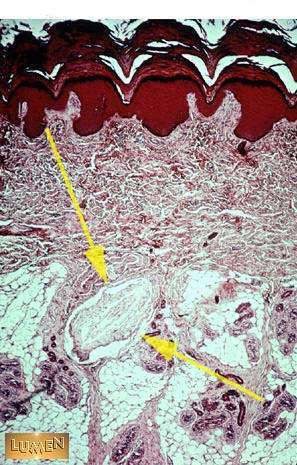

Pacinian corpuscle